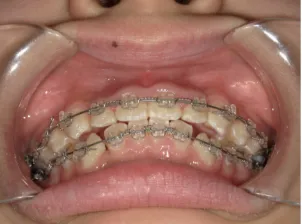

*マルチブラケット法移行前

*マルチブラケット法移行後

治療中④中1:治療中 マルチブラケット法へ移行